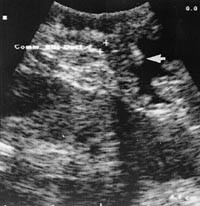

For fremstilling av intrahepatiske og proksimale ekstrahepatiske galleganger benyttes med fordel leveren som optisk vindu, mens man for undersøkelse av midtre og distale del plasserer transduseren direkte på ligamentum hepaticoduodenale. Kompresjon av gallegangen må unngås, eventuelt brukes fysiologisk saltvann intraabdominalt som akustisk vindu. Den beste fremstilling av den intrapankreatiske del av gallegangen og papilla Vateri får man ved å plassere transduseren på lateralsiden av duodenum med lyskrystallet i retning papillområdet og samtidig komprimere ventrikkelvæske til duodenum (fig 1).

Den intrapankreatiske del av ductus choledochus kan enkelte ganger være vanskelig å fremstille. Denne vanskeligheten kan elimineres ved for eksempel å presse ventrikkelvæske over i duodenum (fig 3), utøve forsiktig kompresjon mot duodenum eller forsøke å skanne denne delen av gallegangen fra lateralsiden av duodenum. En sjelden gang vil det være nødvendig å fjerne CO 2 -gassen fra bukhulen mens undersøkelsen pågår. I vårt materiale lyktes det oss ikke å fremstille denne delen av gallegangen optimalt hos 14 % av pasientene. Dette stemmer godt overens med andre materialer, hvor fremstillingen varierer mellom 87 % og 100 % (17, 18).